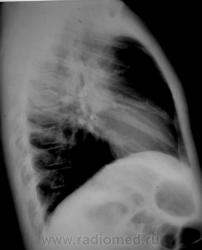

Спасибо за улучшение качества снимков! Все может быть. Но уж больно смущают корни, особенно в боковой проекции

Мне тоже кажется, что корни расширены. Бронхоаденит тут не исключить. Требует дальнейшего обследования, оптимально - КТ груди с внутривенным контрастированием, для лучшей визуализации структур средостения. При отсутствии возможности - линейные томограммы.

Да, и томография нужна, да, и консультация фтизиатра не лишней будет.

Картину можно объяснить ОРВИ - тогда:

- при сохраняющейся избыточности, неоднородности легочного рисунка, расширении корней - ПОСМОТРЕЛ бы (паренхиму заодно) - КТ ОГК!